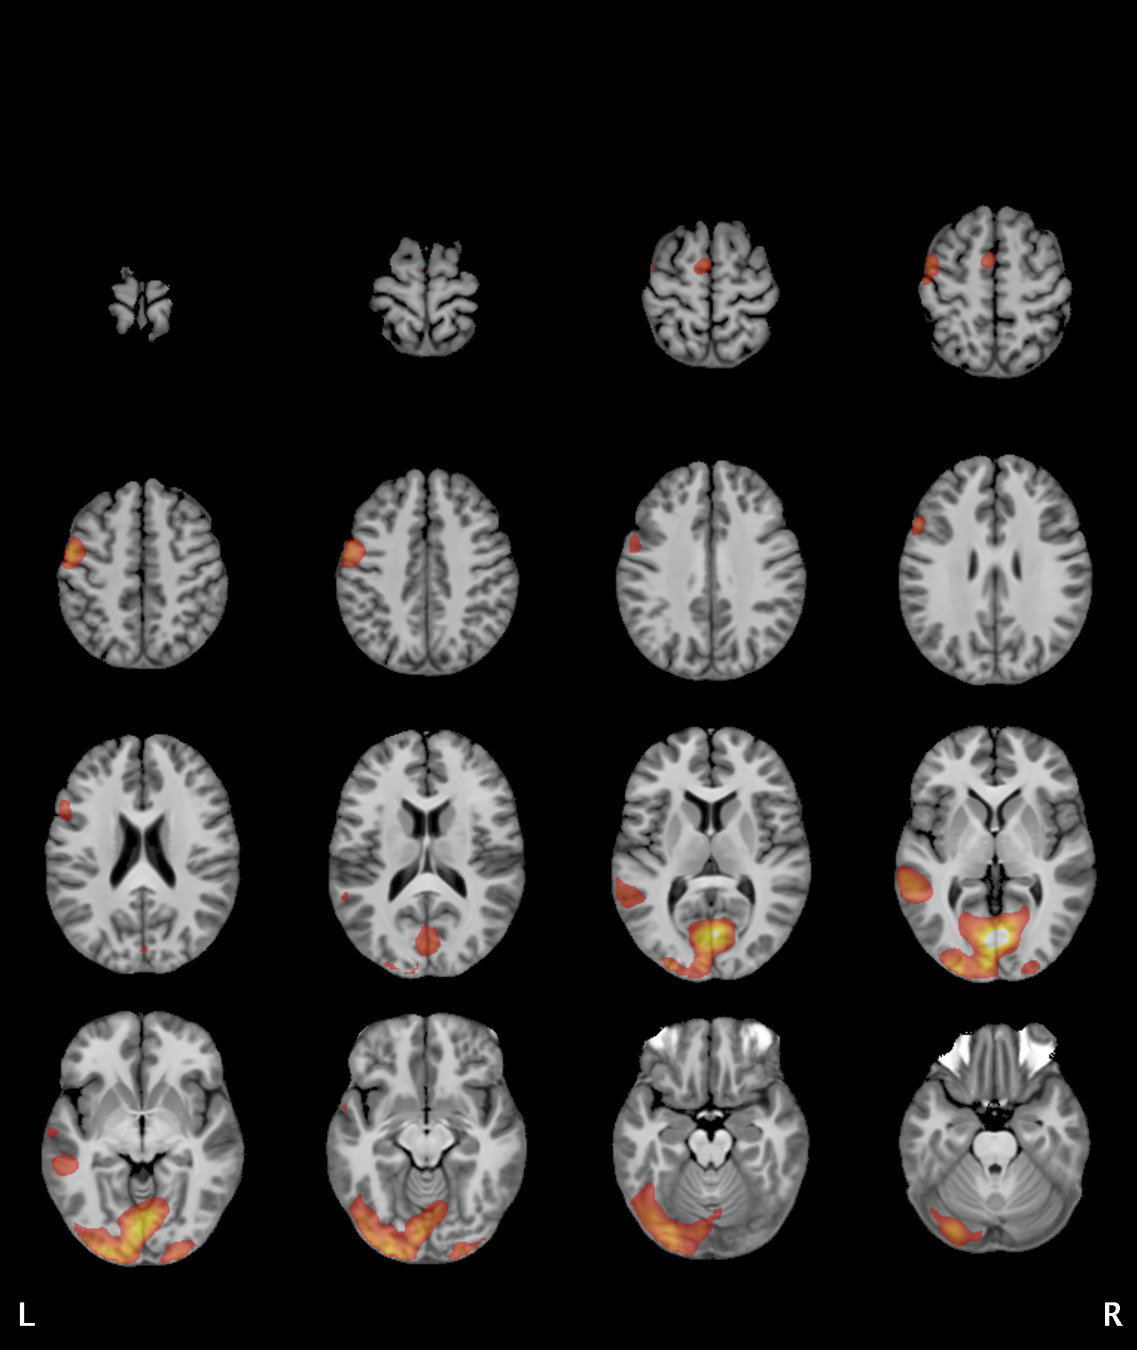

Results

Significant ROIs

Voxels Peak - x Peak - y Peak - z Anatomical location

1923 -1.5 79.5 -9 R/L Lingual Gyrus

495 52.5 -10.5 -18.0 L. Mid. Temporal Gyrus

395 46.5 16.5 33.0 L. Precentral Gyrus

135 1.5 38.5 -12.0 L. Ant. Cerebellum

56 7.5 19.5 -3.0 L. Thalamus

55 -22.5 -94.5 -9.0 R. Inf. Occipital Gyrus

55 52.5 -7.5 15.0 L. Inf. Frontal Gyrus

54 4.5 7.5 60.0 L. Medial Frontal Gyrus

29 -46.5 -7.5 -24.0 R. Temporal Pole